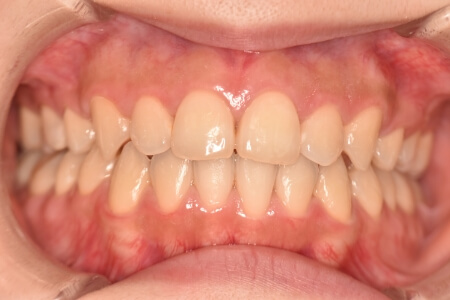

動的治療終了時

症例 症例 症例 症例

検査の結果、開咬を伴うアングルⅡ級1類不正咬合と診断しました。

治療としては、上顎第一小臼歯を抜歯の上、セルフライゲーションブラケット装置(デーモンシステム)とマウスピース型矯正装置(インビザライン)で配列を行いました。顎間ゴムの協力もあり、開咬がきれいに改善されました。

この際、上顎に歯科矯正用アンカースクリューを設置し上顎前歯部後退時の土台としました。

治療期間としては、2年8か月でした。